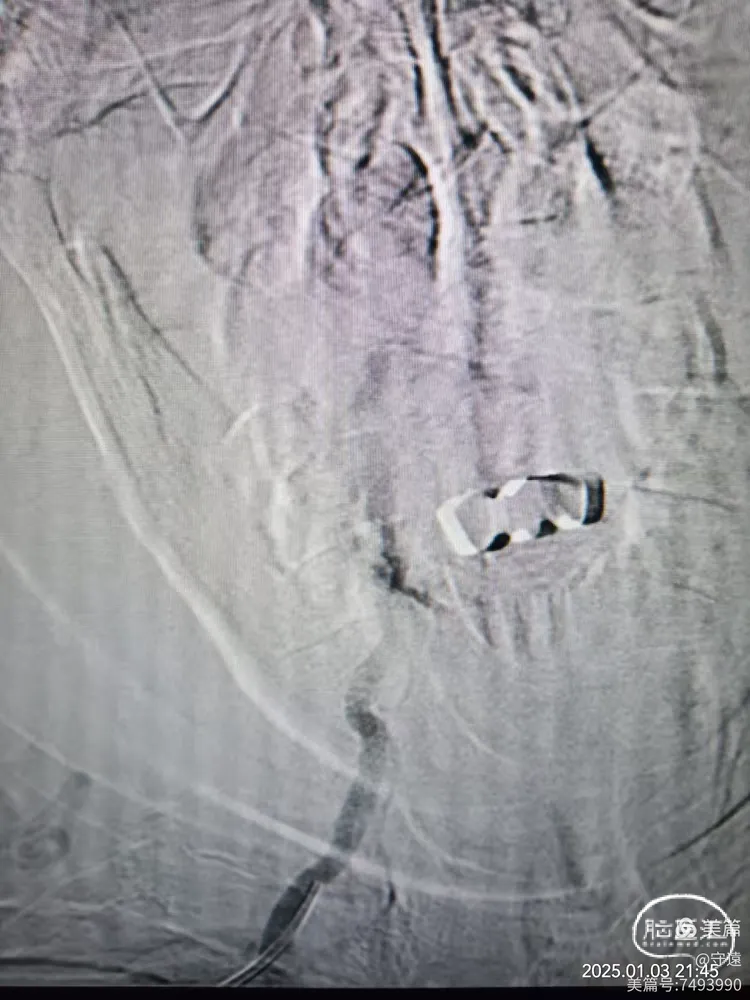

右侧椎动脉顺应,更换6F动脉鞘经桡动脉入路行基底动脉开通。

泥鳅导丝导引6FGT68血栓抽吸导管,泥鳅导丝不出头,内芯支持抽吸导管到达V3段。

踹马桶抽吸出小块硬质血栓。